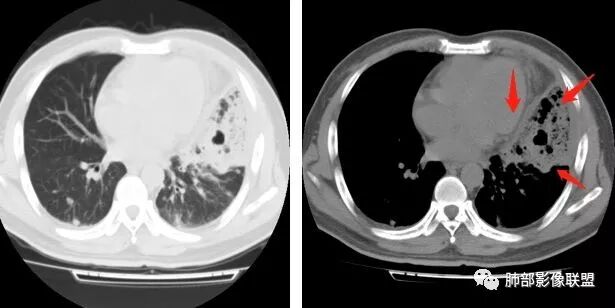

胸 CT

腹增强CT

南边:胸膜下,类圆形,边界清,内有坏死,典型的反晕征,支气管壁增厚不明显,支持血道来源脓毒栓子所致梗死、感染

血道来源没问题

左下叶大片类似病灶

南边:反晕征是毛霉菌的特点按理单从影像:毛霉菌更多符合因为细菌性的特点:液气平面,囊,这个没出现

肺克的影像表现(唐绍宏总结):分布:单侧上叶病变,以右肺上叶多见;患者长期卧床则双脚下肺后基底段分布(国外下肺多见,可能与平均寿命长,卧床及住托老机构多有关) ;如多叶段病变,则以肺上叶后段或下叶后基底段为最明显形态:气管壁增厚、磨玻璃、小叶实变、节段实变、大叶实变,坏死小空洞(直径小于2cm) ,少量胸腔积液50%、脓胸20%特点:早期气管壁增厚较明显、广泛,越靠近病灶越明显,越靠近肺门越明显,见于实变病灶外,偶尔见于磨玻璃影内(支气管通气征) ;未经抗生素治疗,实变病灶内无支气管通气征;早期即可出现坏死,无论坏死还是空洞,绝大多数直径小于2cm (可能与此菌有厚夹膜有关,参考隐球菌)